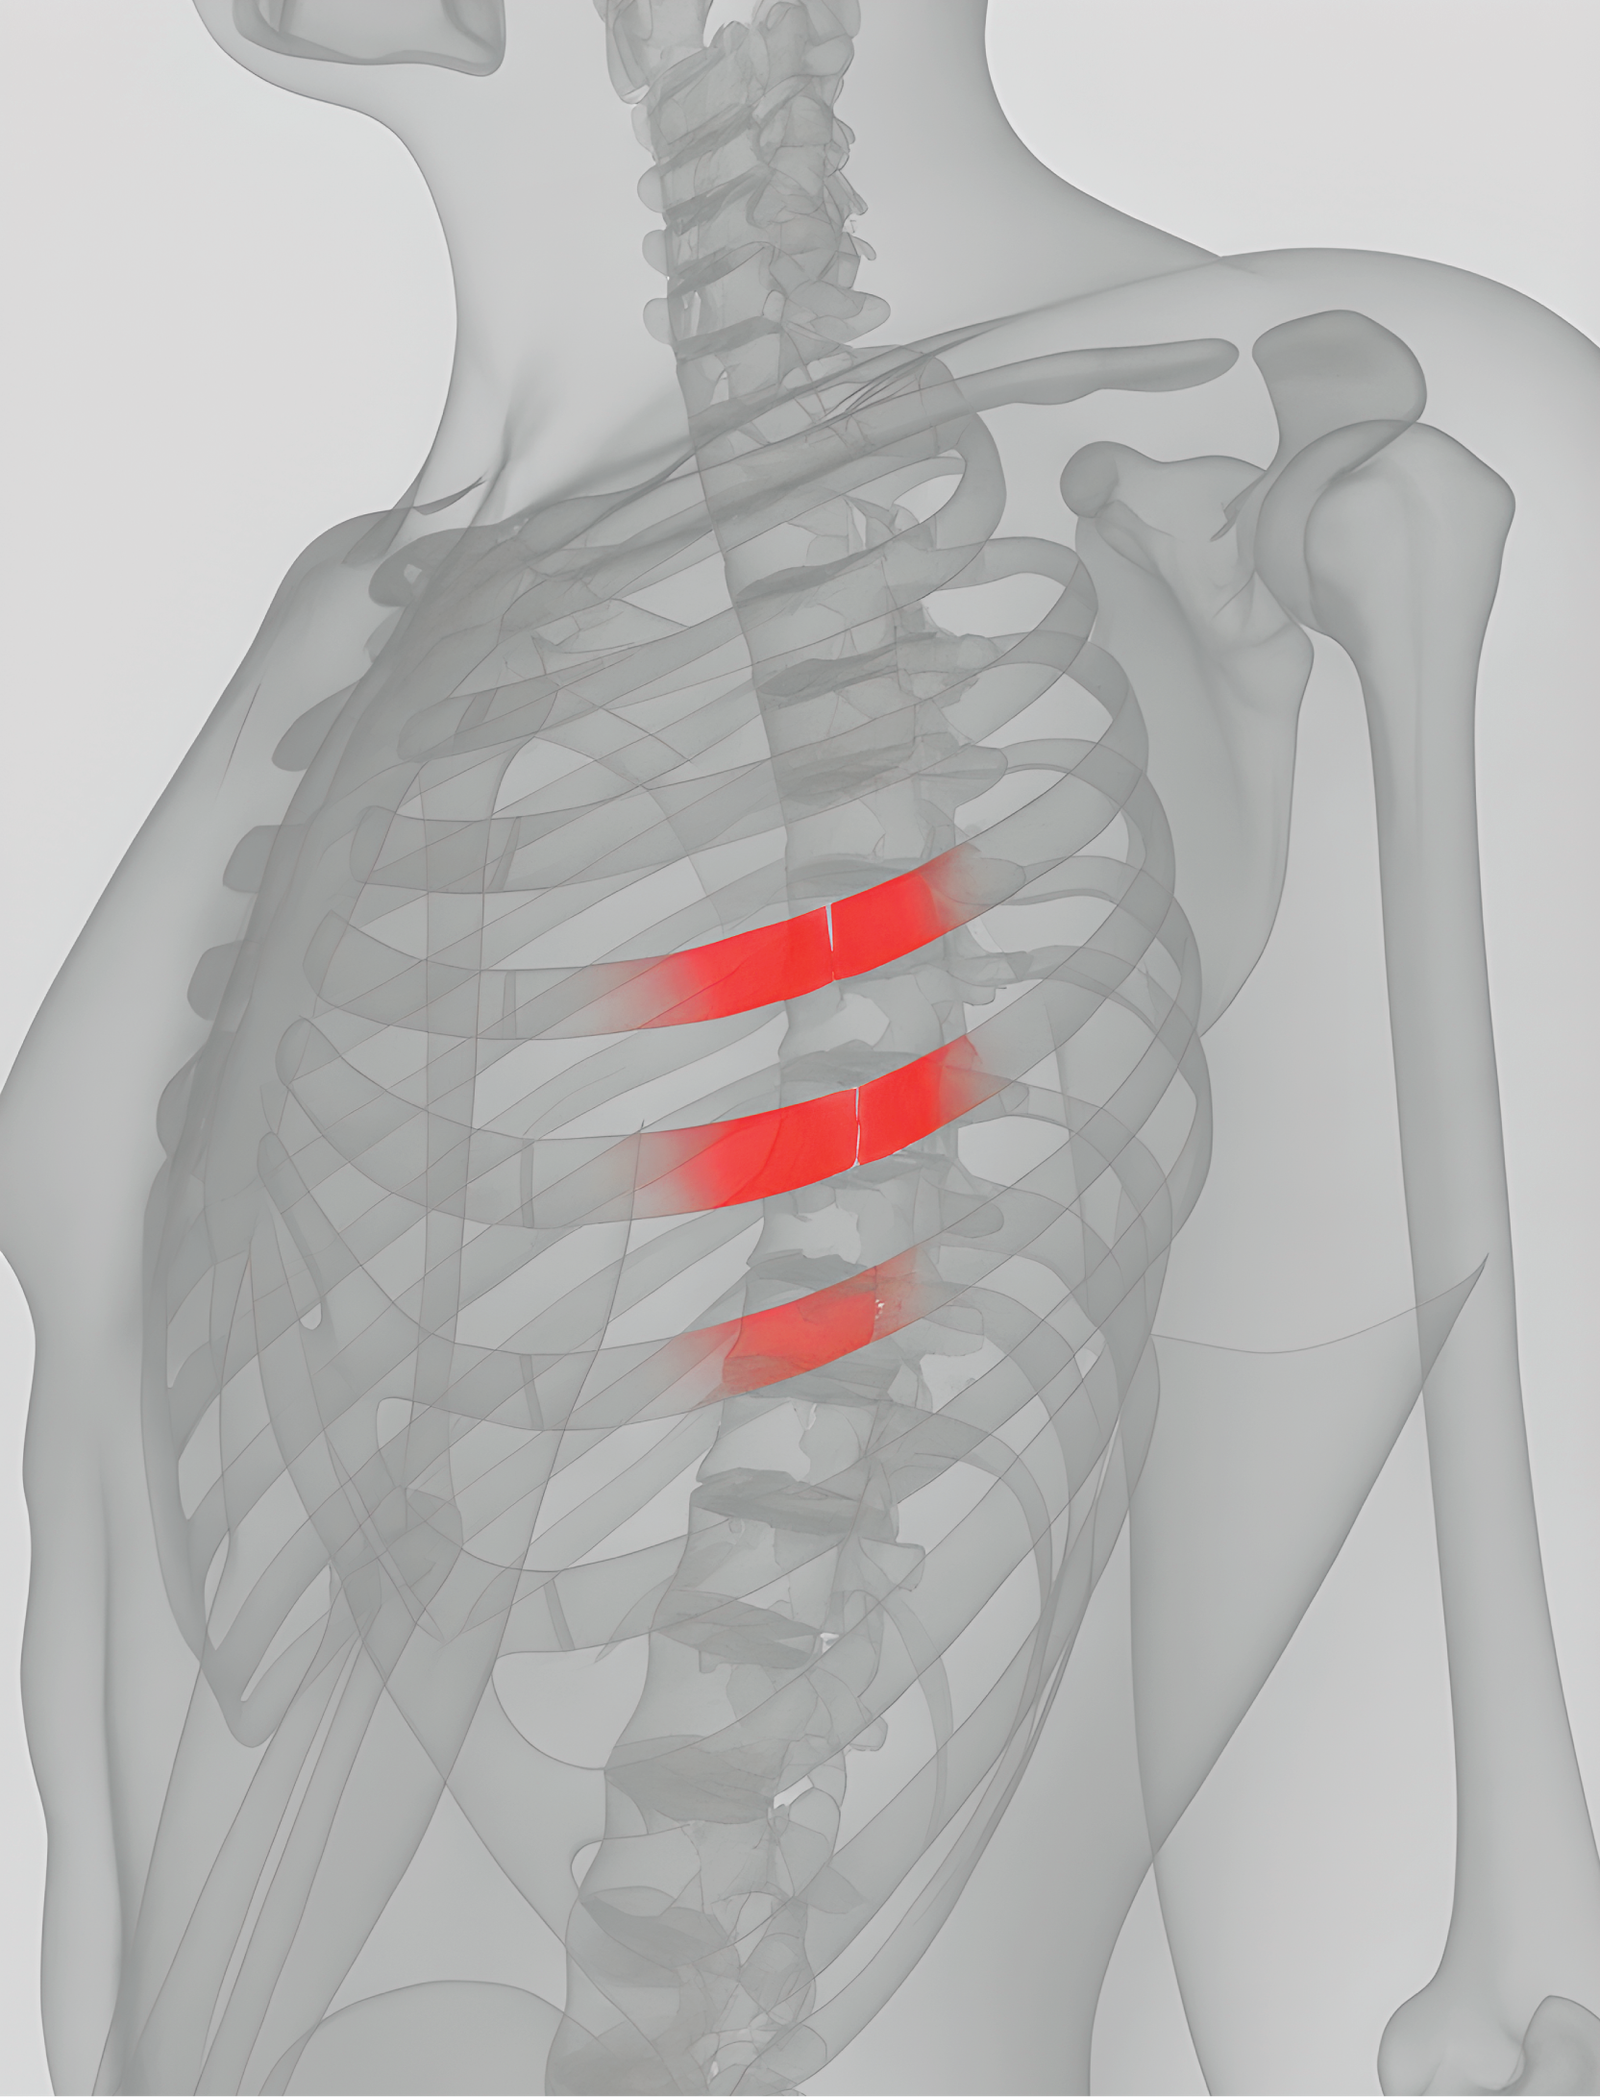

Die Herausforderung bei der Versorgung von Rippenfrakturen

Rippenfrakturen gehören zu den häufigsten Thoraxverletzungen und gehen oft mit starken Schmerzen, eingeschränkter Atmung und begrenzter Mobilität einher.

Diese instabilen Rippenbewegungen verlängern nicht nur die Genesungszeit und verringern die Lebensqualität, sondern erhöhen auch das Risiko für schwerwiegende respiratorische Komplikationen wie Atelektasen und Pneumonien erheblich. Das Schließen dieser Versorgungslücke ist entscheidend für die Verbesserung der Patientenergebnisse und die Gewährleistung einer sichereren und schnelleren Rückkehr in den Alltag.